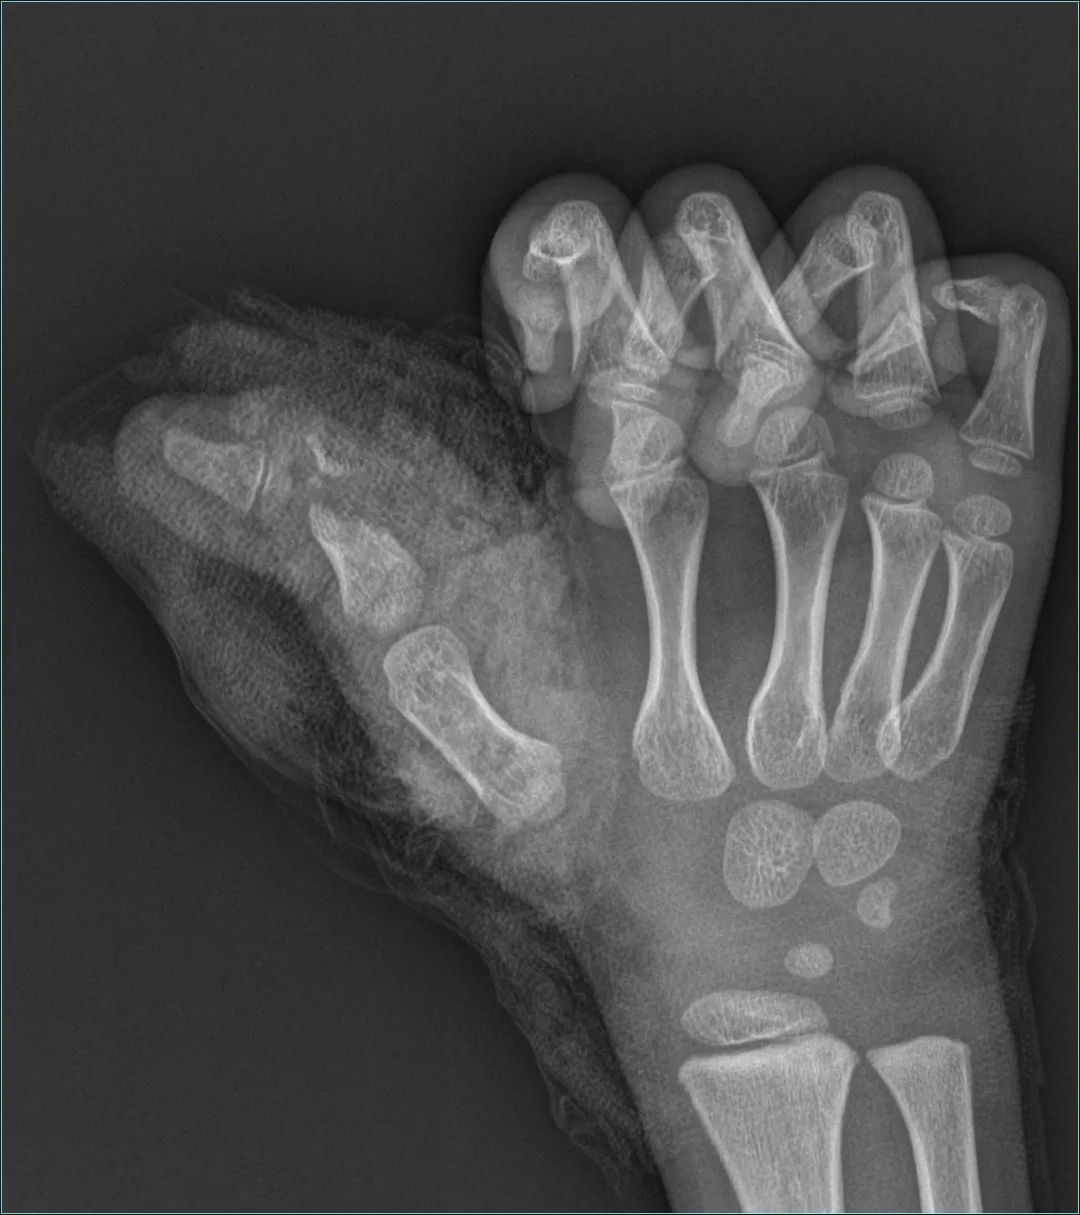

昊昊被緊急送到醫(yī)院后,立即完善相關檢查,檢查可見昊昊右手大拇指骨頭粉碎嚴重,大拇指關節(jié)處離斷僅橈側部分皮膚相連,肌腱斷裂外露,雙側血管神經(jīng)斷裂,刻不容緩,需要馬上進行手術!

向左滑動查看手指傷勢圖片

由于昊昊的指骨被絞得粉碎,若沒處理好,將會影響孩子日后大拇指關節(jié)的正?;顒?,包括后期關節(jié)功能,可能影響到孩子的一生。所以當務之急是將碎片骨頭拼接回來,并妥善固定,但是這項工作難度極大,需要術者具備非常精巧的“手藝”,也要十足的耐心。

葉為義主任凝神靜氣,透過顯微鏡,在指間這一片小小的天地之間,揮灑著盡致的工匠精神:小心翼翼拼湊碎骨后,再逐一完美固定,而后修復斷裂的肌腱,吻合斷裂的神經(jīng)、血管,修補破損的皮膚。時間一點一滴流淌,在高超嫻熟的技術之下,一切進展得無比順利。經(jīng)過近兩個小時的全力以赴救治,手術成功完成。